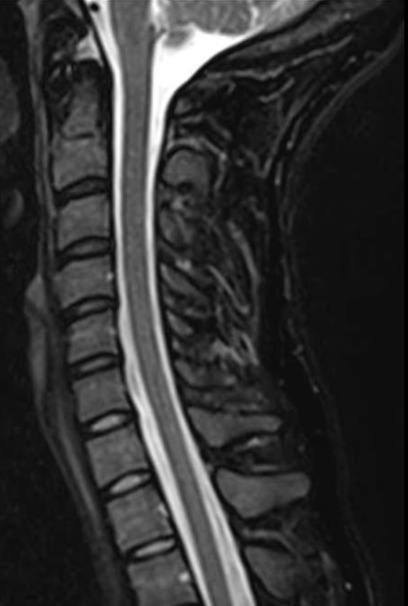

颈椎

- 颈椎影像 — 细致的亚专科复查

- 椎管狭窄 — 了解您的影像结果

- 脊椎滑脱 — 结合临床背景的亚专科判读

- 椎间盘膨出 — 专家影像分析

避免不必要的脊柱手术